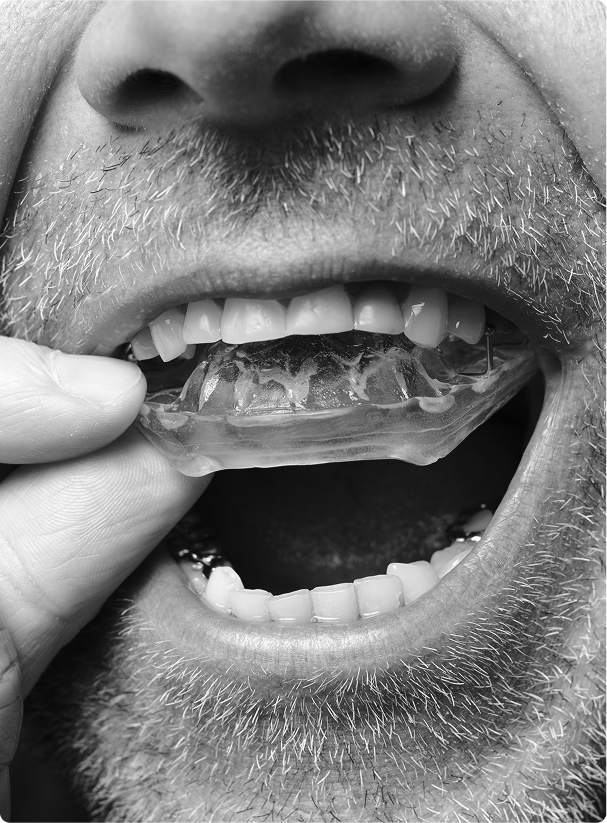

Gouttière Michigan:

une solution sur mesure

Le traitement le plus couramment recommandé en cas de bruxisme est le port d’une Gouttière Michigan nocturne. Cette gouttière, portée la nuit, agit comme une protection entre les dents, tout en permettant une meilleure détente musculaire.

À notre clinique, la fabrication de la plaque se fait à l’aide d’un scanner intraoral, qui remplace les empreintes traditionnelles. Cette technologie nous permet de :

- Réaliser des empreintes numériques en quelques minutes, sans inconfort ;

- Obtenir une précision optimale pour un ajustement parfait ;

- Accélérer le processus de fabrication ;

- Offrir une solution plus confortable et durable.

La plaque est fabriquée sur mesure dans un laboratoire spécialisé, puis ajustée en clinique pour assurer une adaptation parfaite à votre bouche.